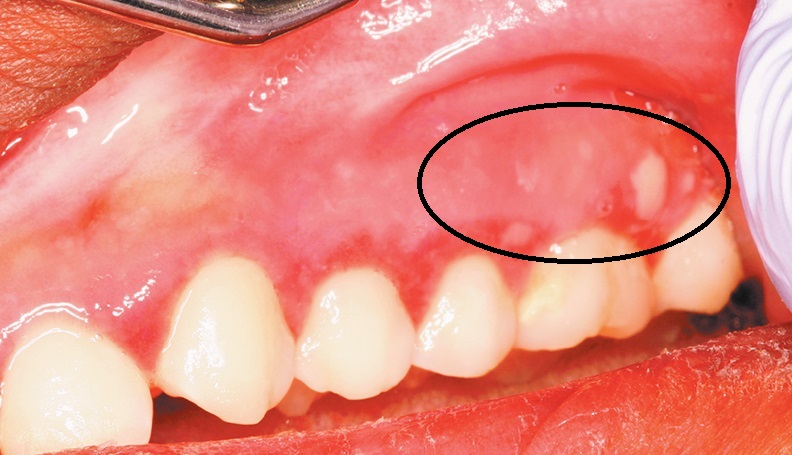

Из-за сходства новообразования слизистой оболочки с распространенными стоматологическими болезнями, часто не удается распознать рак дёсен. Особенно в самом начале формирования опухоли. В этом заключается главная опасность заболевания.

1 стадия – появление незначительных кровоточащих ранок на слизистой. На ощупь десна слегка уплотнена, с преобладанием белой пигментации.

2 стадия – новообразование развивается до достижения примерно 1-2 см в диаметре. Цвет меняется на красно-багровый. Опухоль может уже поражать костную ткань. Однако по этим симптомам точный диагноз поставить трудно. Проявление метастаз не происходит.

Как выглядит десна при образовании опухоли:

- Десенные ткани изменяют внешний вид (появление эрозии, незначительного нароста красноватого цвета с белыми пигментированными пятнами);